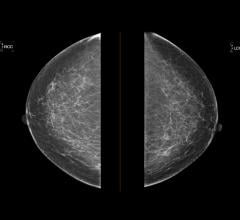

May 3, 2023 — ScreenPoint Medical announced today that its Transpara breast AI has surpassed 4 million mammograms (2D ...